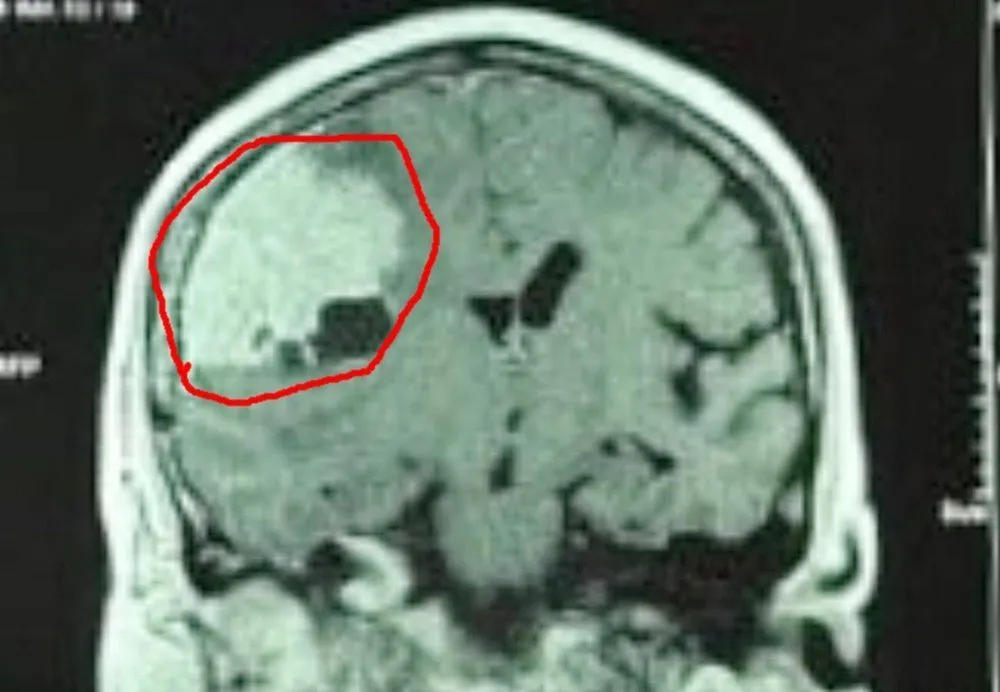

Tại BV, BS ghi nhận bệnh nhân đau đầu và yếu nửa người bên trái. Kết quả chẩn đoán phát hiện u màng não lớn vùng thái dương bên phải, có nhiều mạch máu nuôi u.

Khối u màng não có kích thước khổng lồ, to hơn quả trứng vịt. Ảnh: BVCC |

Trước phẫu thuật, BS đánh giá khối u màng não có quá nhiều mạch máu nuôi nên phải hội ý với BS chuyên khoa can thiệp nội mạch (DSA). Sau đó các BS tiến hành tắc mạch nuôi u để hạn chế máu chảy khi phẫu thuật.

Ở ca bệnh trên, khối u phát triển rất to do bệnh kéo dài mà không được phát hiện. Vì thế khi mổ, ê kíp phải cần sự phối hợp của BS can thiệp nội mạch, làm tắc các mạch máu nuôi chằng chịt trước khi lấy u. Điều này giúp ca phẫu thuật an toàn và tỷ lệ thành công cao hơn.